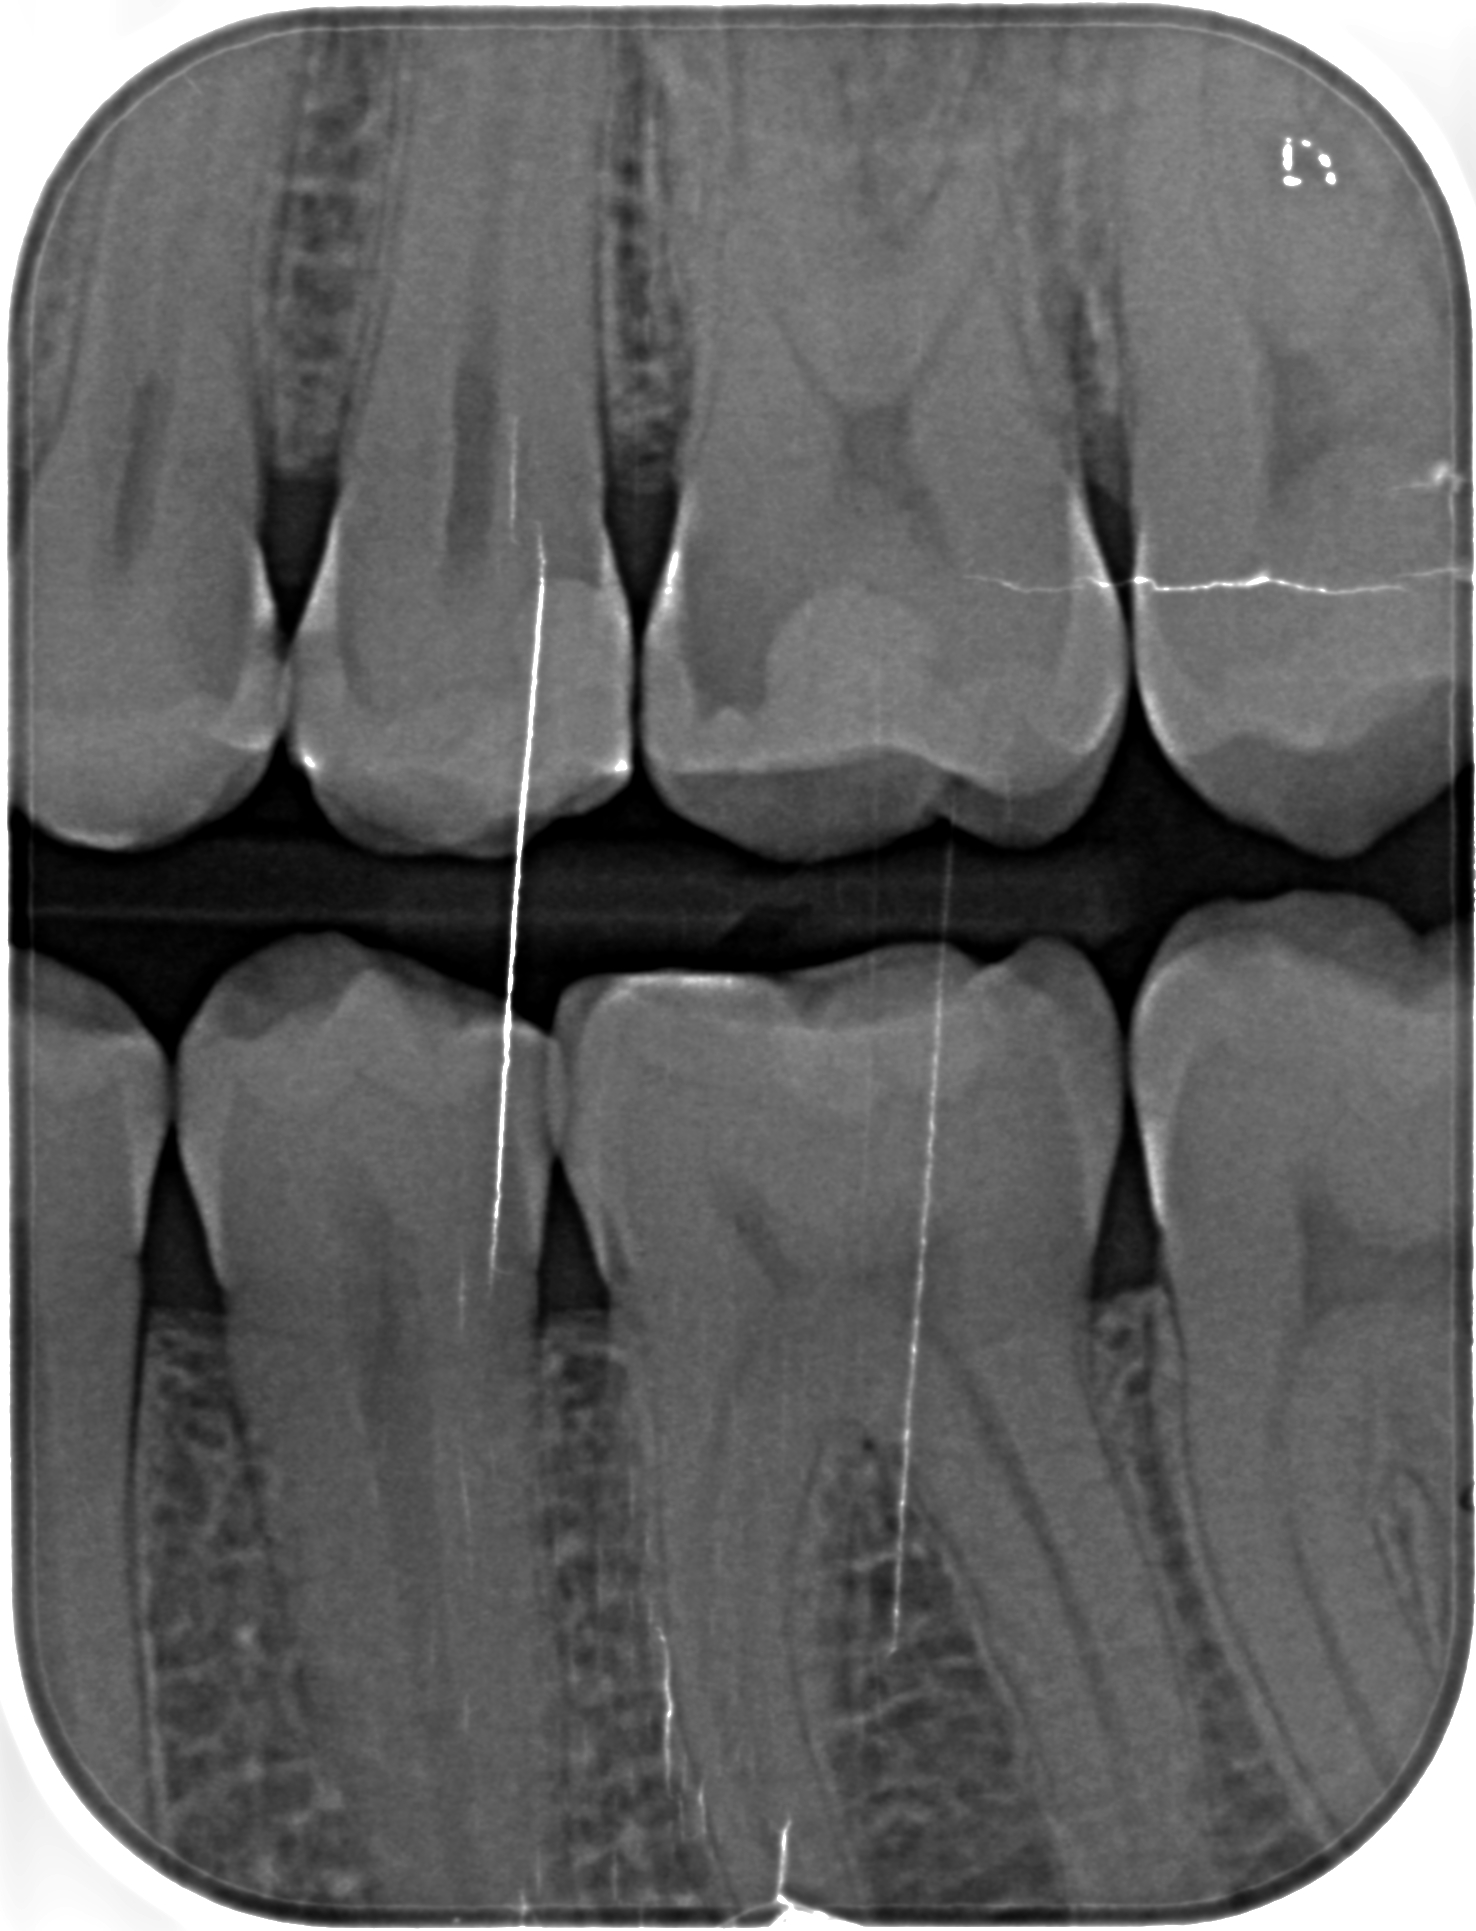

ho fatto una visita dal dentista dove ad occhio nudo ha visto qualche carie e ha poi pensato di fare le lastrine che ho riportato sotto, dove ci vede 7 carie.

Ho fatto poi una seconda visita da un altro dentista dove ad occhio nudo non ha visto niente (strano perchè le igeniste dentali vedevano una carie) ma nelle lastrine ha visto 5 carie

mi potete dire quante carie ci vedete voi e se sono negli stessi denti indicati negli schemi allegati?